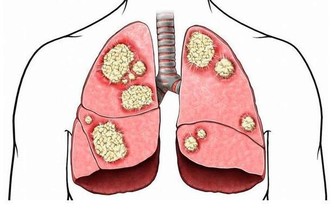

當頸椎曲度病態變直或扭曲,椎體間隙受擠壓而變小,椎間盤受擠壓而膨出,椎體骨質增生,

會刺激神經,誘發眩暈、頭痛、手臂麻木,甚至截癱。